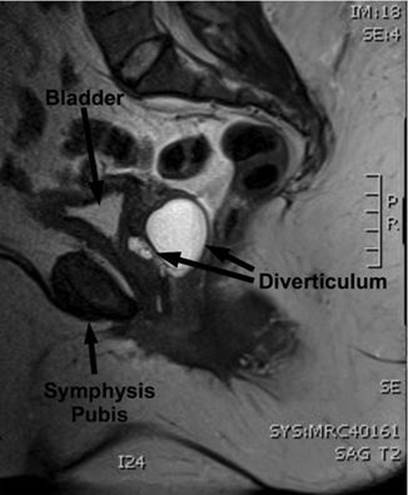

A number of imaging techniques have been applied to the study of female UD. Currently available techniques for the evaluation of UD include double-balloon positive-pressure urethrography (PPU), voiding cystourethrography (VCUG) (Fig. 11.4), intravenous urography (IVU), ultrasound (US), and magnetic resonance imaging (MRI) (Fig. 11.5), with or without an endoluminal coil (eMRI). MRI has become the imaging modality of choice in many centers due to its relatively noninvasive nature, and ability to visualize the anatomy in multiple planes [30–32].

Fig. 11.5

Sagittal MRI demonstrating a urethral diverticulum